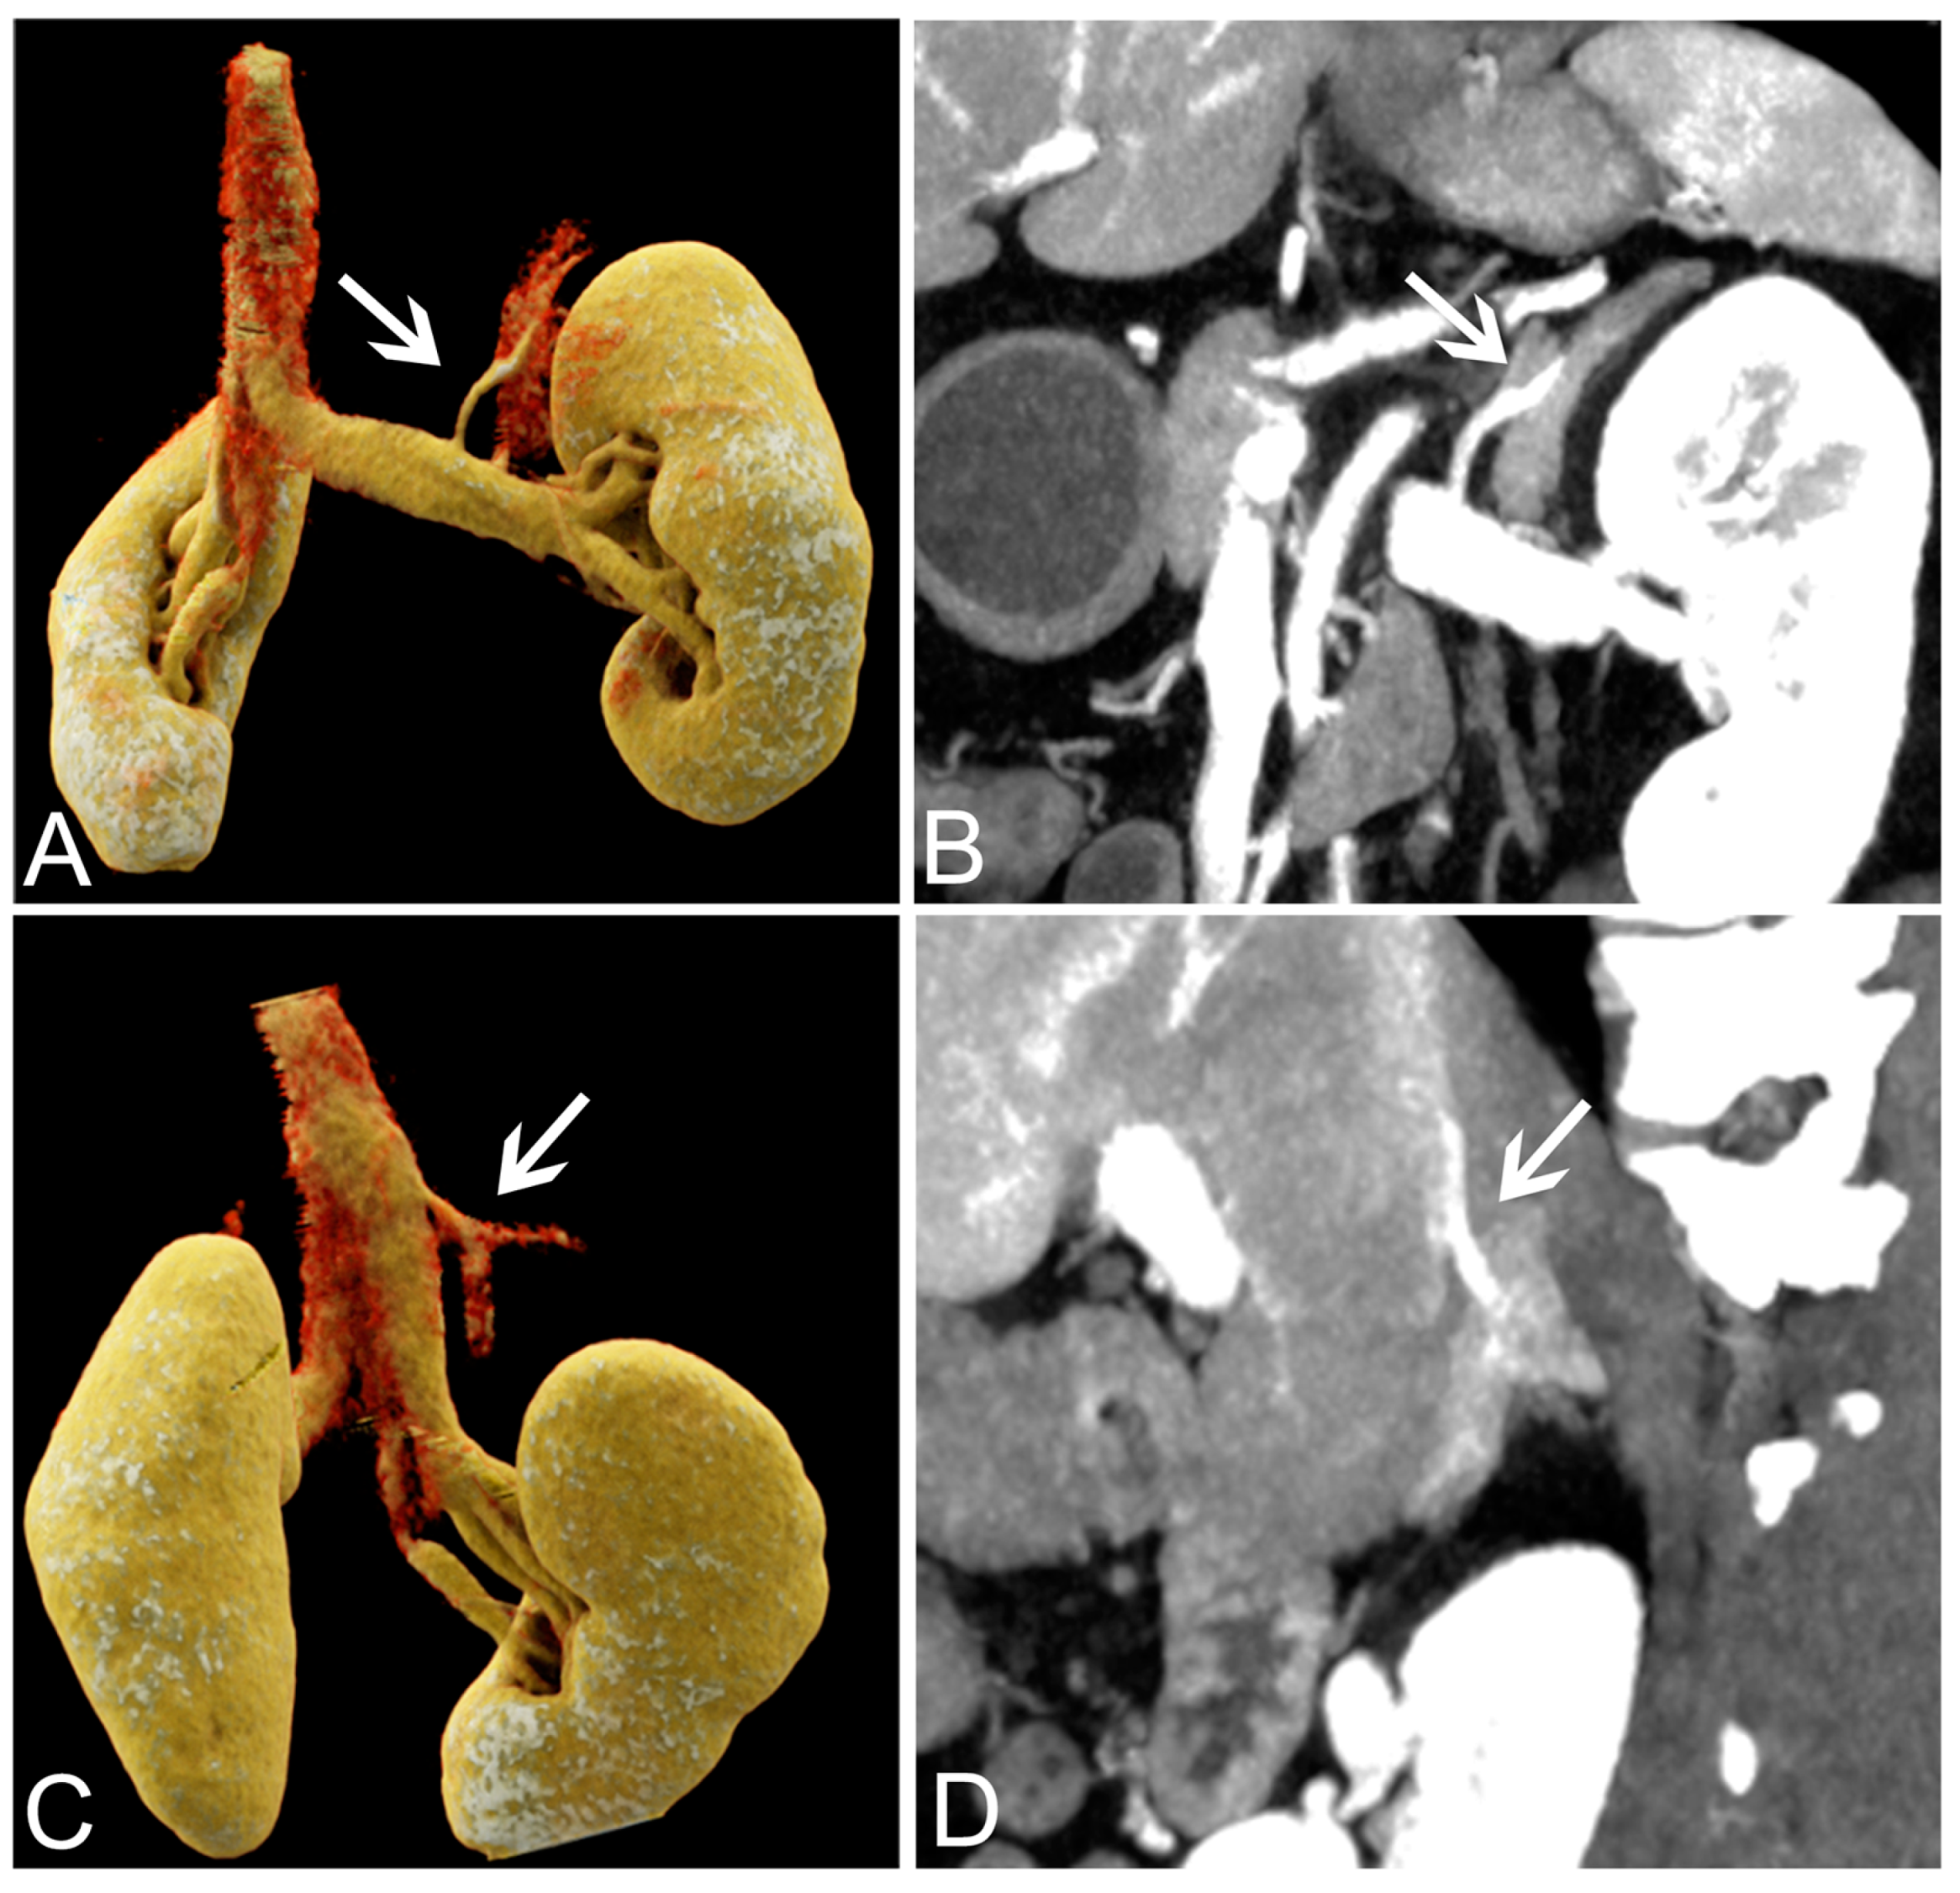

| 40 keV VMI+ | 50 keV VMI+ | 60 keV VMI+ | 70 keV VMI+ | 80 keV VMI+ | |

|---|---|---|---|---|---|

| Right Adrenal Vein | |||||

| 4 (excellent) | 26 | 3 | 3 | 0 | 0 |

| 3 (good) | 13 | 31 | 15 | 4 | 0 |

| 2 (fair) | 0 | 5 | 21 | 6 | 7 |

| 1 (poor) | 0 | 0 | 0 | 29 | 32 |

| detectability | 100% (39/39) | 87.18% (34/39) | 46.15% (18/39) | 10.26% (4/39) | 0% (0/39) |

| score | 4 (4,4) | 3 (3,3) | 2 (2,3) | 2 (2,2) | 1 (1,1) |

| p | <0.01 * | <0.001 * | <0.001 * | <0.001 * | |

| kappa | 0.80 | 0.86 | 0.86 | 0.73 | 0.80 |

| Left adrenal vein | |||||

| 4 (excellent) | 24 | 7 | 0 | 0 | 0 |

| 3 (good) | 14 | 30 | 25 | 10 | 0 |

| 2 (fair) | 1 | 2 | 14 | 26 | 20 |

| 1 (poor) | 0 | 0 | 0 | 3 | 19 |

| detectability | 97.44% (38/39) | 94.87% (37/39) | 64.11% (25/39) | 25.64% (10/39) | 0% (0/39) |

| score | 4 (4,4) | 3 (3,3) | 3 (2,3) | 2 (2,3) | 2 (1,2) |

| p | 0.008 * | <0.001 * | <0.001 * | <0.001 * | |

| kappa | 0.79 | 0.87 | 0.89 | 0.78 | 0.89 |

| Image Quality | p | Kappa | |

|---|---|---|---|

| 40 keV VMI+ | 3 (3,4) | <0.001 * | 0.86 |

| 50 keV VMI+ | 5 (5,5) | 0.72 | |

| 60 keV VMI+ | 3 (3,3) | <0.001 * | 0.72 |

| 70 keV VMI+ | 2 (2,3) | <0.001 * | 0.77 |

| 80 keV VMI+ | 2 (1,2) | <0.001 * | 0.85 |